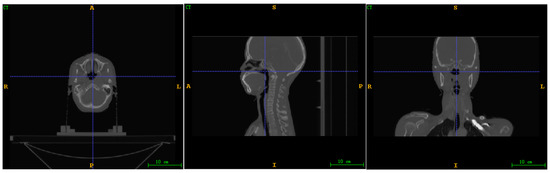

The original image dimensions of each CT scan (patient) were 512 × 512 × Z   ( Z ( 87 ,   132 ) ) ; Z represents the height of the upper and lower spatial images, and the size Z of each CT scan is not the same. The voxel space size is anisotropic. In the preprocessing stage, we mainly use SimpleITK (https://simpleitk.org/, accessed on 1 April 2023) to process images, which is usually used to process some common medical image format files. We resampled the experimental image to achieve isotropy. After processing, the voxel space size and image dimensions will be changed, as shown in Table 1. Figure 2 shows the effect of the processed image. The software we use for visualizing the entire data is ITK-Snap [33]. The dataset contains 80 CT scans from 80 patients, i.e., one CT scan for one patient. To demonstrate that reinforcement learning can learn from limited data, we trained with 50 CT scans (from 50 patients), and the remaining 30 CT scans (from the other 30 patients) were used for testing. For the test set, the labels are used for algorithm evaluation, not for the inference procedure.

Figure 2. Schematic diagram of data processing.